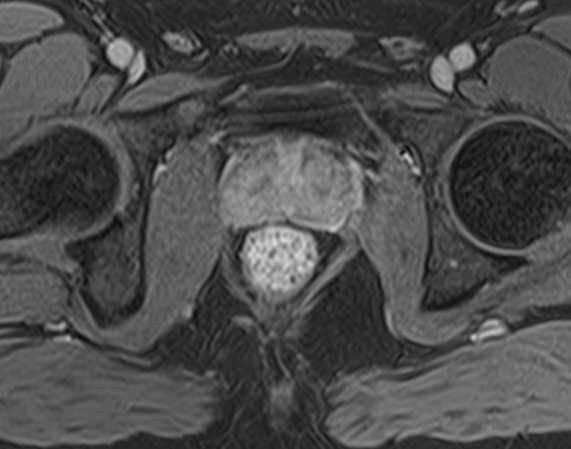

Простата расположена в труднодоступной для диагностики анатомической области, однако метод магнитно-резонансной томографии позволяет детально изучить структуру органа и окружающих ее тканей, включая семенные пузырьки (секреторные органы, вырабатывающие жидкую часть семенной жидкости) и семявыносящие протоки.

При подозрении на опухолевый процесс в предстательной железе в обязательном порядке проводится контрастное усиление. Это подразумевает внутривенное введение контраста, созданного на основе соединений металла гадолиния. Степень и характер накопления контрастного препарата в органах и тканях позволяет различать патологические процессы, в том числе диагностировать опухоли на ранних стадиях, что повышает шансы на успешное лечение.

В клинике «Доступная медицина» диагностика заболеваний предстательной железы выполняется при помощи современного высокопольного магнитно-резонансного томографа экспертного уровня TOSHIBA VANTAGE TITAN 1,5 Тесла. Аппарат производит сканирование в виде послойных тончайших срезов с шагом от 1 мм и преобразует их при помощи инновационных компьютерных программ в изображения трехмерного формата. Методика позволяет получить максимально полную картину о состоянии структуры простаты и окружающих тканей и поставить точный диагноз.